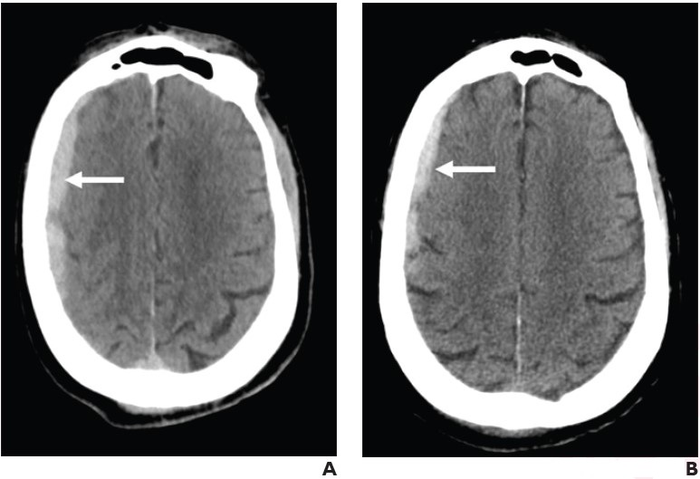

Leesburg, VA, March 24, 2022 According to ARRS’ American Journal of Roentgenology ( AJR ) , antithrombotic therapy was not linked to increased incidence of traumatic intracranial hemorrhage on CT in adult patients, although the therapy did show association with hematoma expansion at follow-up.

Vardar and colleagues’ retrospective case-control study included 1,630 patients (693 female, 937 male; mean age, 80 years) who underwent head CT after presenting to the emergency department (ED) with ground-level fall (Glasgow Coma Scale ≥ 14 and no focal neurological deficit) between January 1 and December 31, 2020. Initial head CT examinations were reviewed for traumatic intracranial hemorrhage characteristics and follow-up head CT examinations (performed within 24 hours) were reviewed for hematoma expansion, with clinical outcomes extracted from medical records.

The frequency of intracranial hemorrhage after ground-level fall with good neurological status was not significantly different between patients on antithrombotic therapy and those not on antithrombotic therapy (4.4% vs 3.1% respectively, p = .24). However, hematoma expansion occurred more frequently in patients on antithrombotic therapy (26.2% vs 4.8%, p = .04).

Also noting no significant difference between patients on anticoagulant therapy alone, antiplatelet therapy alone, or both, “the frequency of midline shift and regional mass effect was not significantly different between patients on antithrombotic therapy and control patients,” the authors of this AJR article added .